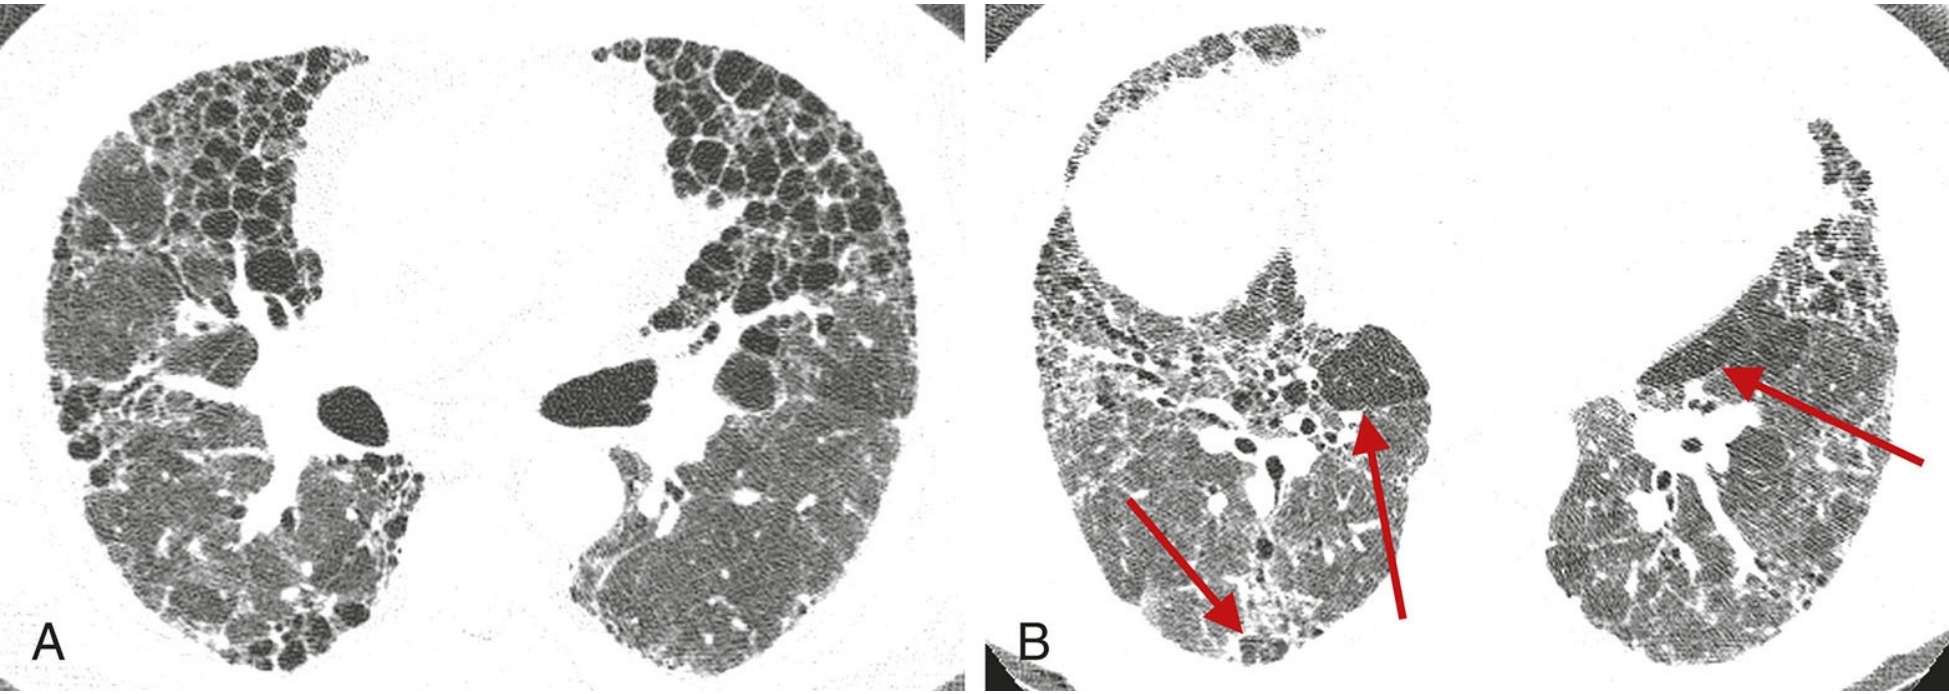

d9aa28845b7cba2a1759d5760b020659.png

异常病变的HRCT分布特征在诊断中的价值。

A.纤维型非特异性间质性肺炎相关的硬皮病患者,HRCT显示以肺外周及胸膜下区分布为主的异常表现;

B.结节病患者,HRCT异常表现主要分布在肺门区及支气管周围,而相对未累及胸膜下区。对于慢性症状的病例,胸膜下及肺基底部分布为主的病变提示普通型间质性肺炎、非特异性间质性肺炎或脱屑性间质性肺炎。弥漫性或者中心轴分布是间质性肺炎的不典型分布,提示其他疾病,如过敏性肺炎或结节病。